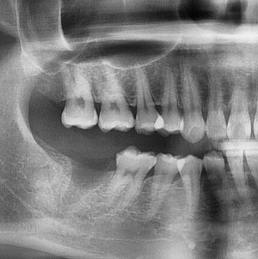

Losing a tooth due to severe decay or infection is more common than most people think. In many cases, the tooth may be too damaged (“rotten”) to save, and removal becomes the best option to prevent further pain or infection.

🦷 Why You Shouldn’t Wait Too Long

After a tooth is removed, your body begins to heal — but at the same time, changes start happening in your mouth:

The bone where the tooth used to be begins to shrink

The neighbouring teeth may start shifting

The opposing tooth (above or below) may start to over-erupt (supra-eruption)